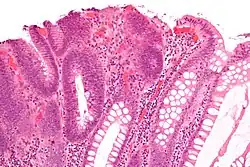

Mikroskopický obraz

Dysplazie je charakterizována následujícími základními mikroskopickými změnami buněk:

- Anizocytóza (různá velikost buněk)

- Poikilocytóza (buňky různých tvarů)

- Hyperchromatismus (excesivní pigmentace)[2]

- Přítomnost mitotických figur (zvýšený počet buněk podstupujících mitózu).[3]